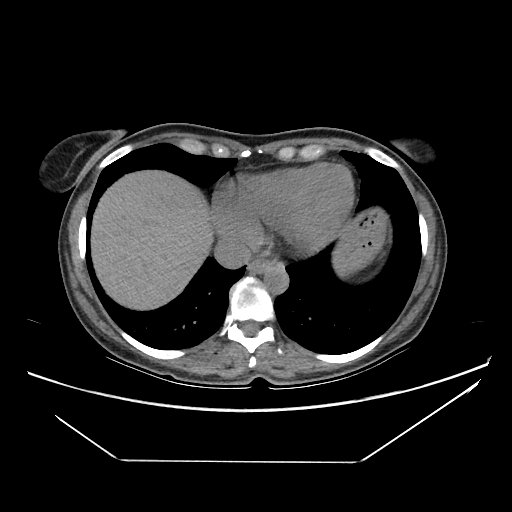

Generated VENOUS CT scan (A→B translation)

Full window (WL 1023.5, WW 4095 β†’ Low βˆ’1024, High +3071)